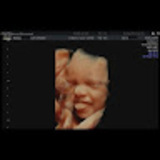

4d baby scan for pregnant women Baby moments is a private pregnancy clinic both owned and run by professional, de